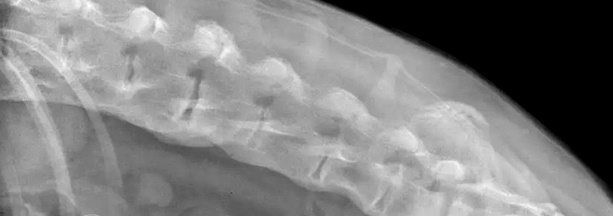

Η διάχυτη ιδιοπαθής σκελετική υπερόστωση αποτελεί μια βαρύτερη μορφή της παραμορφωτικής σπονδύλωσης. Ακτινολογικά παρατηρείται αποτιτάνωση (και σχηματισμός νέου οστού) στην κοιλιακή και πλάγια επιφάνεια τριών ή περισσοτέρων γειτονικών σπονδυλικών σωμάτων. Το μεσοσπονδύλιο διάστημα έχει φυσιολογικό εύρος και δεν απεικονίζονται αλλοιώσεις που να υποδηλώνουν πάθηση μεσοσπονδύλιου δίσκου (π.χ. σκλήρυνση του σπονδυλικού σώματος, φαινόμενο κενού, αποτιτανωμένο υλικό του δίσκου μέσα στο σπονδυλικό σωλήνα). Δεν παρατηρούνται ανωμαλίες στις αρθρικές αποφύσεις.

Διάχυτη ιδιοπαθής σκελετική υπερόστωση στην οσφυϊκή μοίρα της ΣΣ. Πλάγια προβολή οσφυϊκής μοίρας ΣΣ που απεικονίζεται ο σχηματισμός νέου οστού στην κοιλιακή επιφάνεια των οσφυϊκών σπονδύλων.